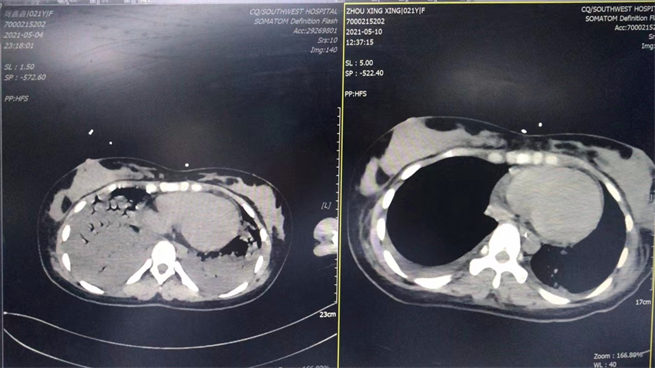

5月4日是剛轉進科時和5月10日是撤ecom后做的CT對比圖。西南醫院供圖!